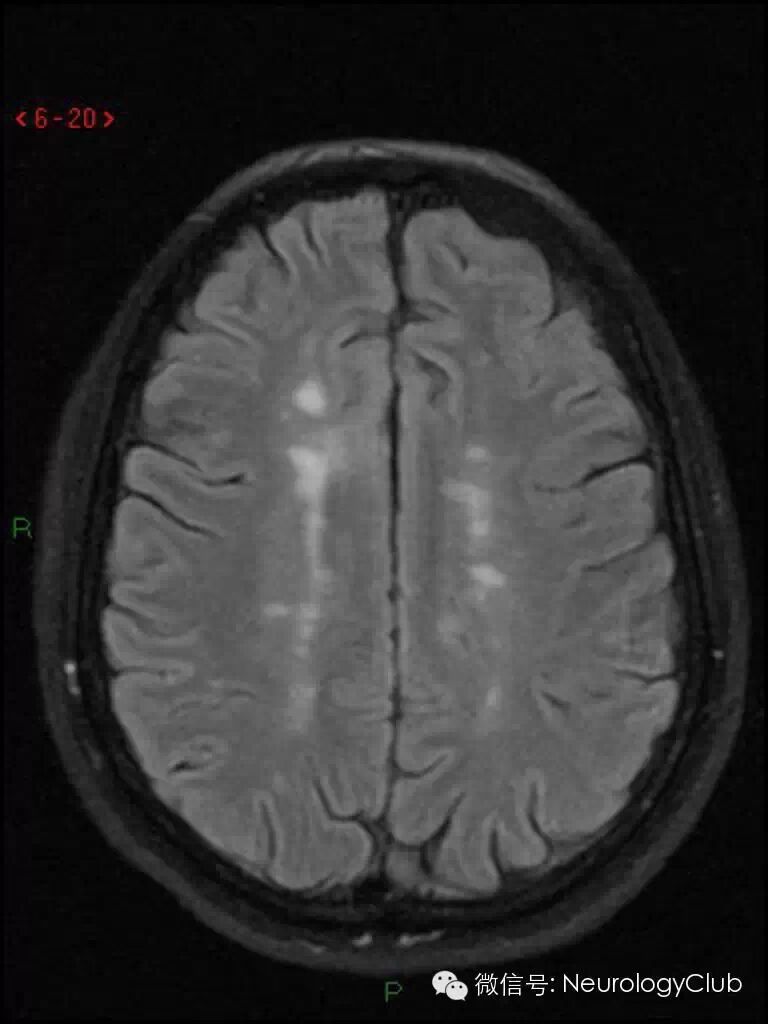

Dawson手指征(Dawson finger sign)

Dawson手指征(Dawson finger sign)为头颅MRI上,T2WI/FLAIR 显示侧脑室旁白质内多发条状、卵圆形、指状或火焰样高信号病灶,其长轴垂直于侧脑室边缘(矢状位也可见病灶累及胼胝体),类似于手掌五指张开的表现。这种征象在矢状位、轴位、冠状位均可以观察到。

Dawson手指征是多发性硬化较为特异的表现,以苏格兰神经病理学家James Walker Dawson命名,以纪念其于1916年首先揭示了多发性硬化的病理改变为侧脑室周围白质内髓鞘崩解和胶质细胞增生。炎性细胞沿充血的小血管周围浸润,形成所谓血管周围袖套。病灶常以小静脉为中心,形态上呈指状改变。